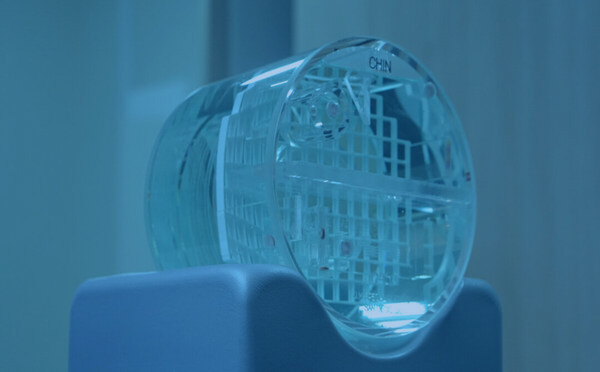

A SERAD atua nas três áreas da Física Médica, sendo elas: Radioterapia, Radiodiagnóstico e Medicina Nuclear. Possuímos objetos teste e materiais de ponta para atuar no controle de qualidade desde aceleradores lineares para tratamentos radioterápicos até o de menor complexidade como o equipamento de raios x odontológico Periapical.